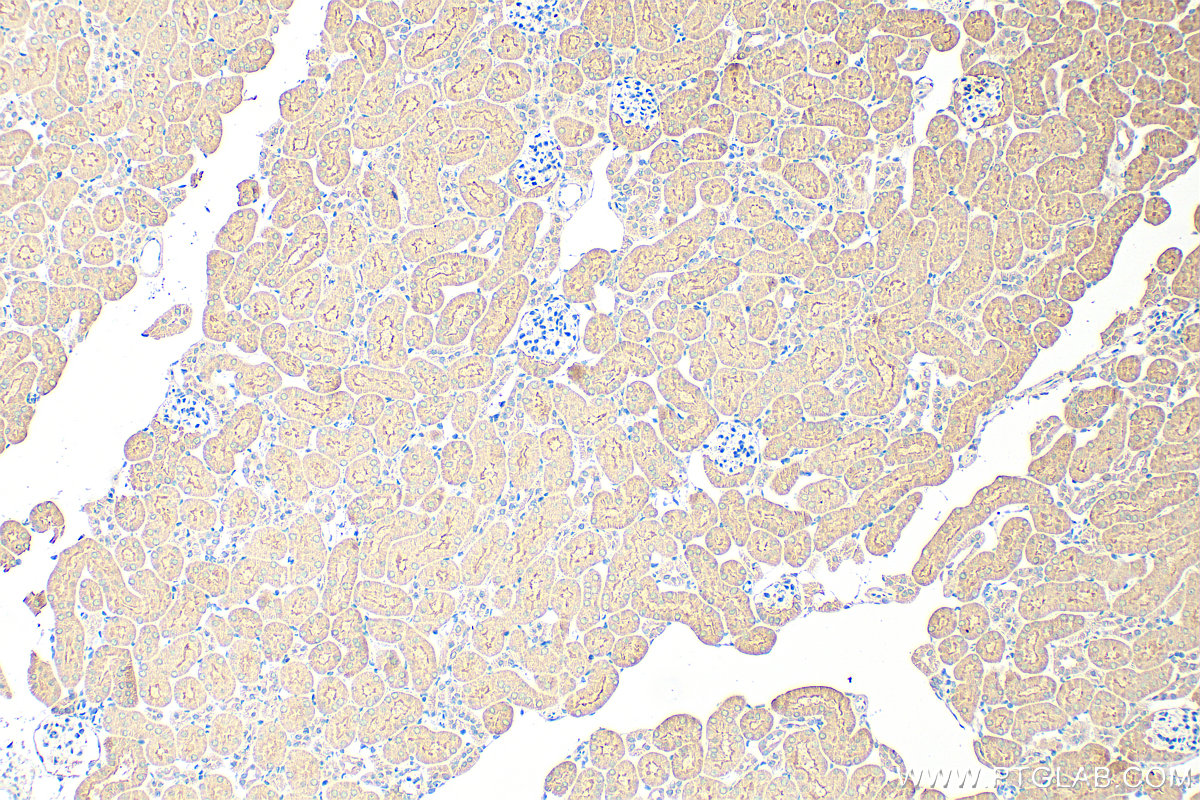

| Positive IHC detected in | rat kidney tissue, human thyroid cancer tissue, mouse kidney tissue, rat ovary tissue Note: suggested antigen retrieval with TE buffer pH 9.0; (*) Alternatively, antigen retrieval may be performed with citrate buffer pH 6.0 |

| Immunohistochemistry (IHC) | IHC : 1:500-1:2000 |